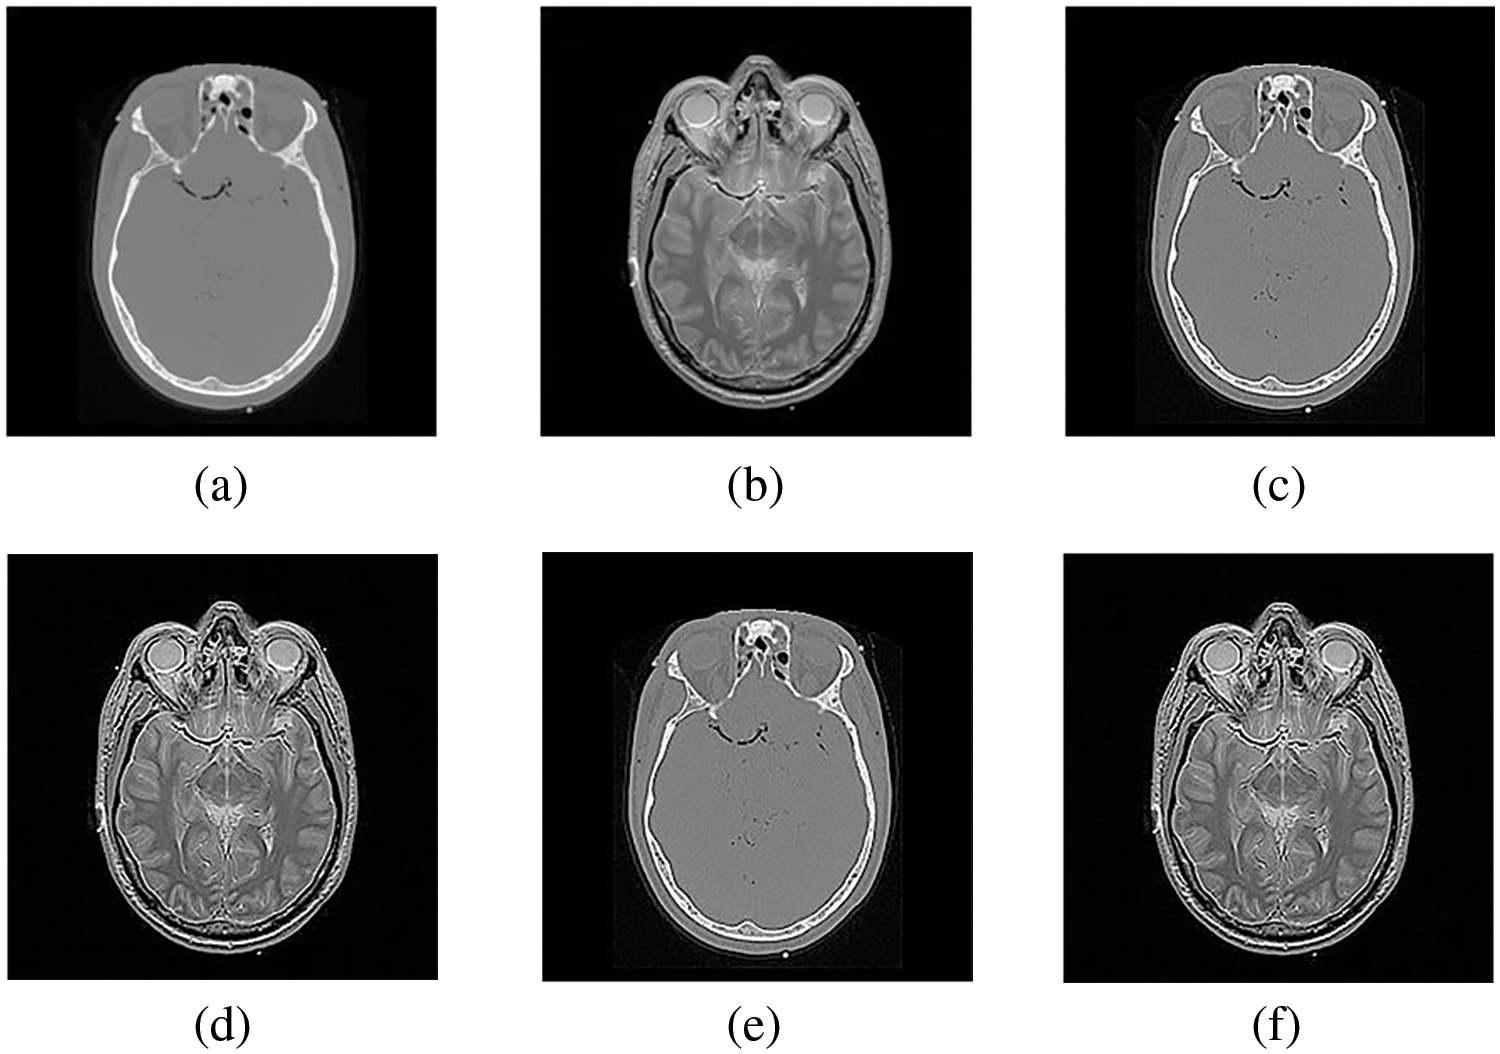

Figs. 4–11 display the original CT and MRI images along with their corresponding enhanced images obtained through the proposed sharpening technique, including Unsharp masking and LF+DFT Sharpen. The enhanced images effectively highlight and enhance minor details, making them clearer and more perceptible. These enhanced images play a crucial role in subsequent stages of the fusion process, where the aim is to integrate the essential information from both CT and MRI modalities.

Figure 3: The sharpened results of “Brain CT, and MRI Image set 1” (a, b) are two source images CT and MRI, respectively, (c, d) are sharpened images by Unsharp masking and (e, f) LF+DFT sharpen images

Figure 6: The difference between (a, b) simple CT and MRI images and (c, d) Sharpen CT and MRI images

Figs. 4–11 present the fused images obtained from both existing and proposed hybrid approaches. The existing approaches, including PCA, MF, DWT, DTCWT, DCHWT and SWT, initially fuse the source images. Then, the SWT method is combined with the proposed sharpening techniques and applied to fuse the sharpened images. Comparatively, the fused images generated by the proposed methods, namely SWT+Unsharp masking and SWT+(LF+DFT), exhibit significant improvements compared to the baseline techniques. To highlight the differences among the fused images and facilitate a better understanding of the enhanced and informative nature of the images, specific areas are marked with red and green boxes in Figs. 3–10. Furthermore, a magnified version of the region marked with the red box is provided in Figs. 5 and 9 to further illustrate the qualitative analysis of brain datasets.

Understanding the difference between simple and sharpened images is crucial. Sharpened images exhibit higher acutance, which is a subjective measure of edge contrast. Acutance cannot be quantified directly; it relies on the observer’s perception of whether an edge has sufficient contrast or not. Our visual system tends to perceive edges with higher contrast as having more clearly defined boundaries. In Fig. 6, we zoom in on specific areas of the images, highlighting them with green and red boxes for simple and sharpened images, respectively. This allows us to easily observe the dissimilarity between the two versions, particularly in the enhanced details visible within the green boxes.